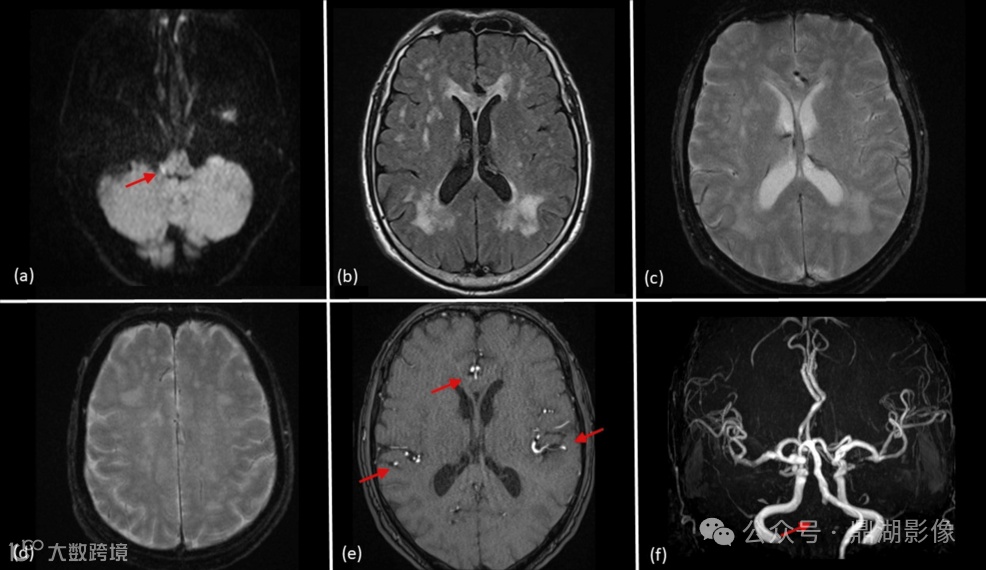

鉴于此,患者行紧急颅脑MRI检查,显示右侧椎动脉闭塞,脑干出现急性缺血性改变,但未观察到脑血流明显异常信号(图1a - 1f)。临床怀疑为急性缺血性卒中。

图 1:入院时的初步MR图像

(a)DWI可见脑干右侧弥散受限,呈急性缺血性改变,与右侧椎动脉供血区域一致(箭头)。

(b)Flair可见双侧侧脑室旁及皮层下脑白质高信号。

(c)T2WI未见异常静脉或动脉充血。

(d)另一层面T2WI未见明显血管异常。

(e)MRA显示除右侧椎动脉外(箭头),动脉血流信号正常。

(f)MIP显示右侧椎动脉无血流,可能与脑干梗死有关(箭头)。